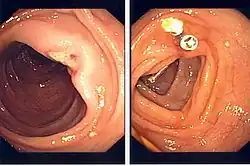

When a treatable lesion is identified on endoscopy (such as a bleeding vessel), an endoclip can be inserted through the channel of the endoscope until the sheathed clip is visible on the endoscopic image, and the handle for deployment handed to the nurse assistant. The clip is unsheathed by retraction at the handle, positioned, and "fired" by the assistant to treat the lesion.